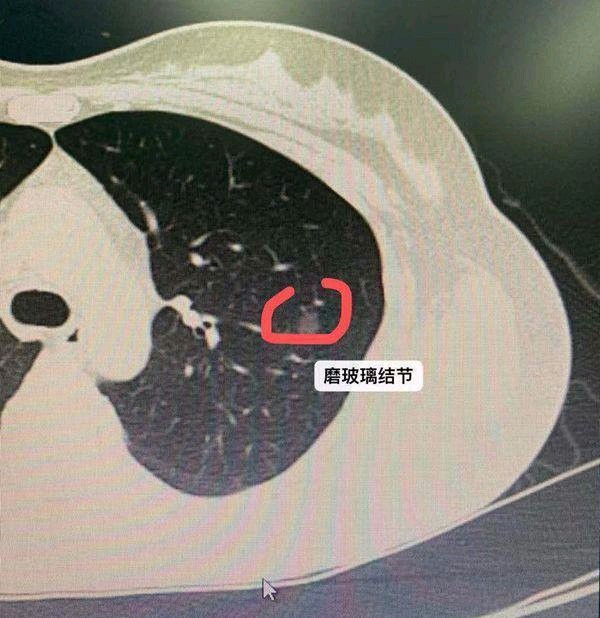

定期进行肺部检查是关注肺结节的重要方法之一。通过 X 光或 CT 扫描等检查手段,可以及时发现肺结节的存在及变化。

2.了解检查结果:认真解读检查报告,了解肺结节的大小、形态、位置等信息。